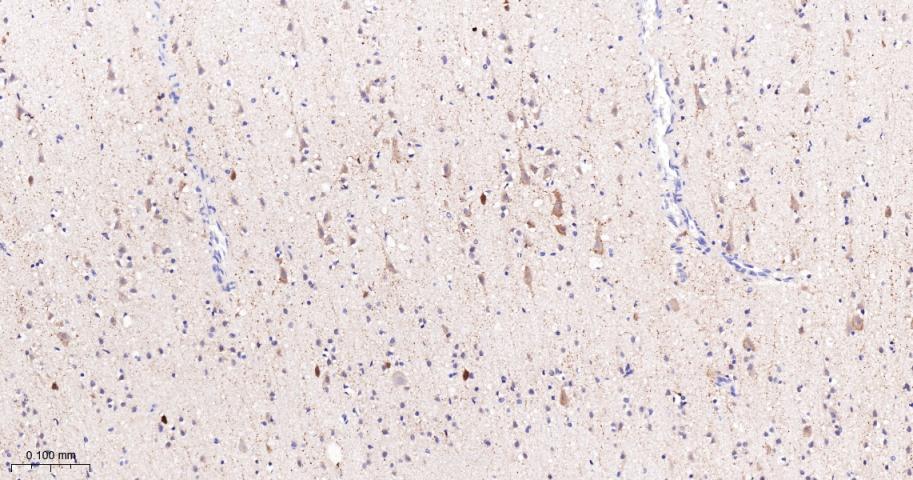

Paraformaldehyde-fixed, paraffin embedded Human Cerebrum; Antigen retrieval by boiling in sodium citrate buffer (pH6.0) for 15 min; The section was incubated with FDFT1 Monoclonal Antibody, Unconjugated (bsm-61816R) at 1:200 overnight at 4°C, followed by conjugation to the bs-0295G-HRP and DAB (C-0010) staining.